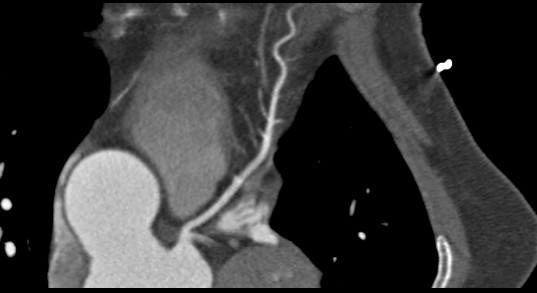

标题: CT24400:患者54岁,心前区不适进行心脏冠脉造影检查。 [打印本页]

标题: CT24400:患者54岁,心前区不适进行心脏冠脉造影检查。

患者54岁,心前区不适进行心脏冠脉造影检查。高手看看有问题没有?